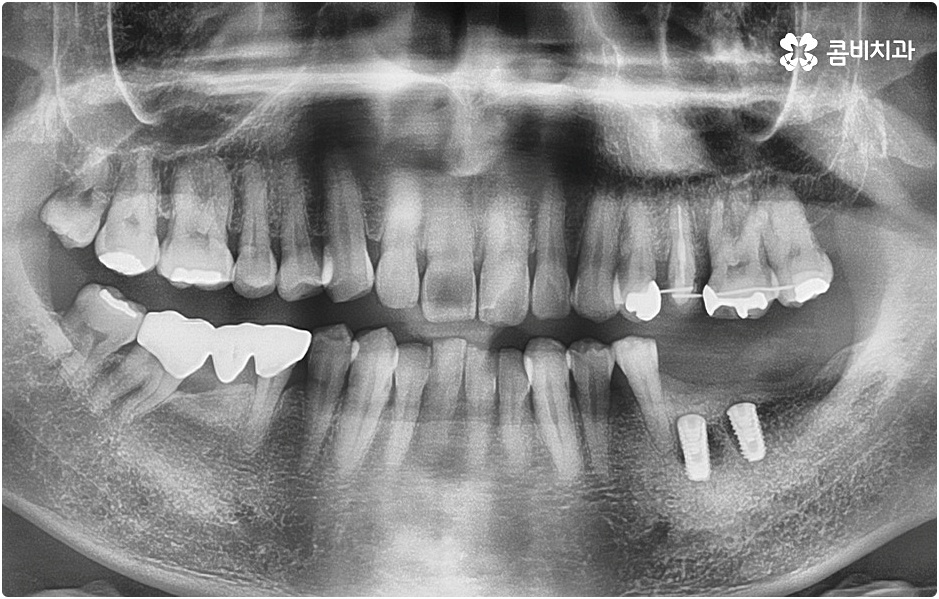

요즘은 치아를 상실했을 때 예전에 많이 이용했던 틀니나 브릿지 보다는 임플란트 시술을 더 선호하시고 있는데요. 임플란트 치아의 저작력 회복이 80~90% 정도이기 때문에 사용하기에 크게 무리가 없고 편안하다는 점 그리고 자신의 원래 자연 치아와 비교해 봤을 때 별로 차이가 나지 않을 정도로 자연스러워서 심미적인 만족도 역시 높다는 점이 대표적인 장점일 거예요. 또한 관련 치의학 기술이 꾸준히 발달해 왔다는 점과 국산 재료 개발을 통해 비용적인 부담이 예전에 비해 많이 줄어 들었다는 점도 임플란트의 대중화에 기여했다고 볼 수 있습니다.

환자분들의 상황에 따라 즉시 임플란트 시술이 가능하지 않은 경우라고 해도 만약 본원과 같이 치과 내부에 자체 기공소를 갖추고 있다면 기간 단축은 물론이고 보다 정교하고 섬세한 보철물 제작 및 혹시 모를 수리와 수정 역시 빠르고 원활하게 이루어진다는 점에서 환자분들의 부담과 불편이 크게 줄어들 테니 너무 걱정하실 필요는 없을 거예요. 또한 임플란트 치아의 경우 정기 검진을 꼬박꼬박 받고 스케일링 치료 등을 통해 주변 잇몸 건강을 철저하게 돌본다면 거의 반영구적으로도 사용할 수 있으니 임플란트 시술 후 일상 생활 속에서 이를 건강하게 유지 관리할 수 있도록 식습관 및 생활 습관, 칫솔질 등에 주의하면서 내원 주기를 잘 맞춰주시길 당부드리고 있습니다.